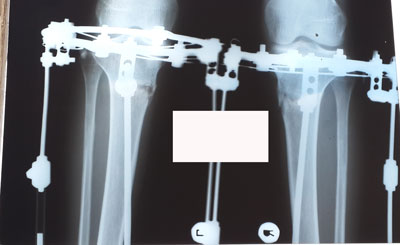

Рентген в 90 дней.

Здравствуйте,Rozali! Приезжайте на снятие аппаратов. Всё отлично! Пересрослось!!!Здравствуйте. Высылаю снимки. Как сращение? Могу приезжать на снятие?